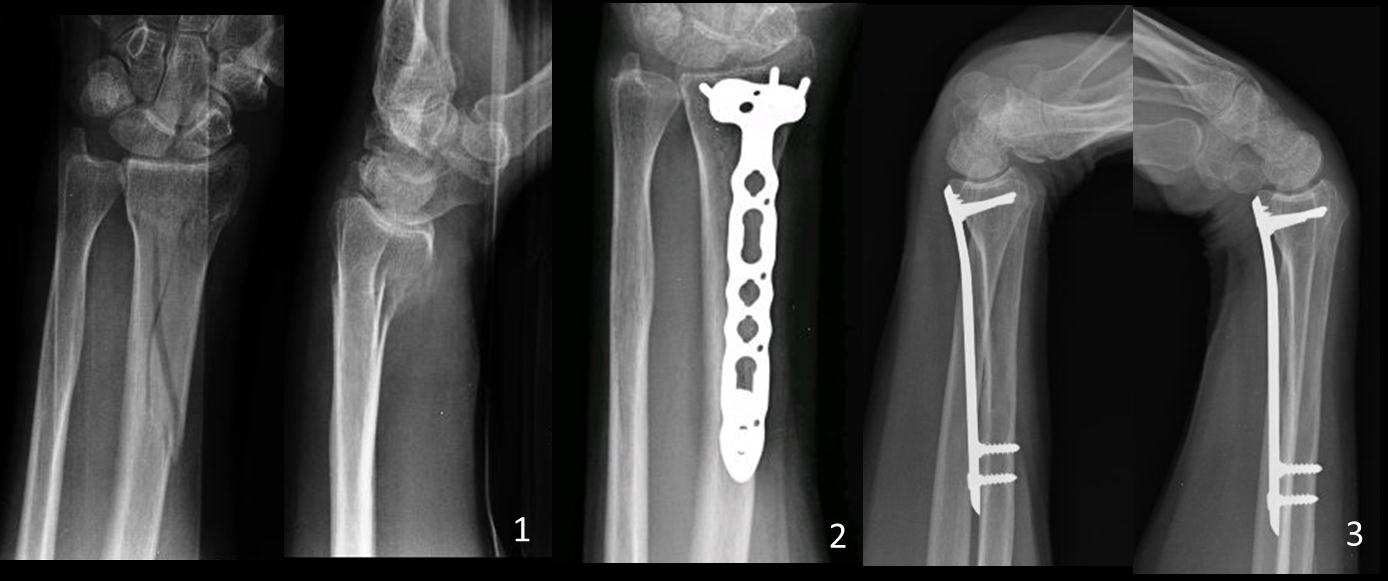

Osteosíntesis percutánea con placas volares bloqueadas en fracturas metafisarias distales de radio Descripción de la técnica y resultados preliminares. [Percutaneous volar locked plate fixation in metaphyseal fractures of distal radius: technical description and preliminary results].